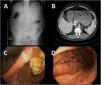

We present the case of a 54-year-old male patient with atrial fibrillation (AF), on treatment with rivaroxaban, flecainide and bisoprolol, who underwent pulmonary vein isolation cryoablation as his AF was refractory to drug management, and was discharged after 24 h without incident. Five days later, he came into the accident and emergency department with vomiting, epigastric pain and abdominal distension. Abdominal X-ray showed dilation of the gastric chamber (Fig. 1A). A nasogastric tube was inserted and intravenous analgesia administered. Abdominal CT scan showed marked gastric distension with no apparent obstructive cause (Fig. 1B). The patient remained under observation and tests were completed with a gastroscopy, where large gastric dilation was identified with only partial assessment of the gastric body due to food debris, but reaching the second duodenal portion without evidence of obstructive cause (Fig. 1C). Twenty-four hours after arriving at the accident and emergency department, the patient was discharged with a low-fat diet and double-dose omeprazole. He was referred to Gastroenterology and levosulpiride was added to his treatment. Repeat gastroscopy showed no evidence of lesions (Fig. 1D). After seven months, the patient is asymptomatic and the treatment has been discontinued.

Figure 1.

(A) Marked dilation of the gastric chamber. (B) Marked gastric dilation with no apparent obstructive cause. Nasogastric tube in gastric chamber. (C) Slow-emptying stomach, patent pylorus. (D) Months later, normal gastroscopy.